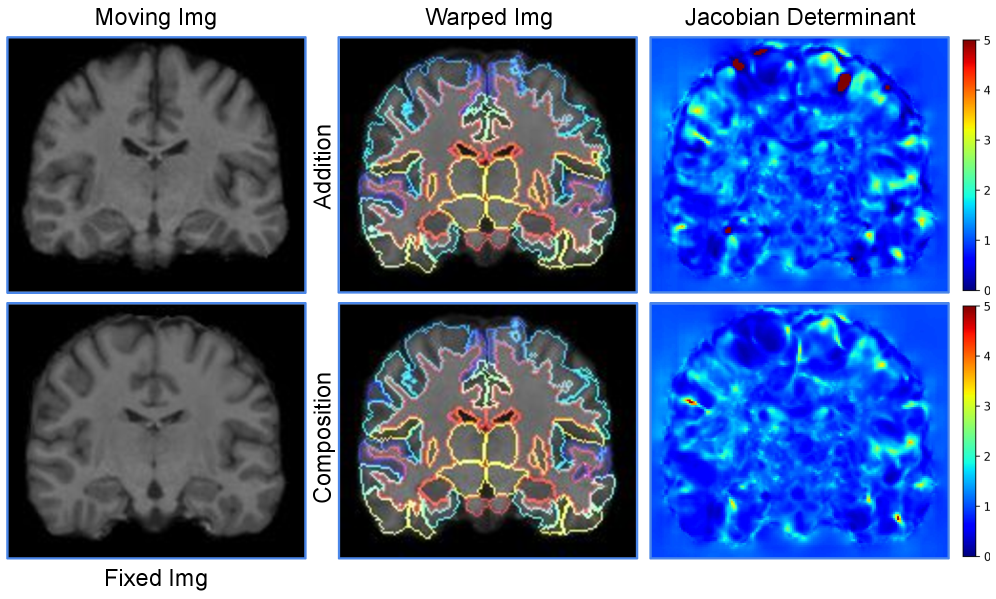

Models using a feature pyramid, which must compose multiple deformation fields from coarse to fine, require more careful handling of integration and composition. For example, LapIRN [56] and MemWarp [81] use a Laplacian feature pyramid and compose deformation fields across levels by addition. While computationally less demanding, this approach can result in a poorer trade-off between deformation smoothness and registration accuracy [12], as well as slower convergence and a tendency to settle at sub-optimal local minima [72].

Unlike cardiac and abdomen datasets with different organ motions, inter-subject brain MR image registration requires fine-grained alignments of multiple variably shaped and sized brain structures. Table III presents the results of semi-supervised learning on the OASIS dataset. With similar field smoothness, EOIR outperforms both LKUNet and TransMorph-2 in Dice score. Note that these models were trained semi-supervisedly, and the results are clearly influenced by the provided segmentation masks during training, as improvements in Dice score often correlate with less feasible deformation fields. The advantage of EOIR in this task primarily lies in the reduction of parameter size. With similar smoothness and a slightly higher Dice score, EOIR reduces network parameter size by 98.1% compared to TransMorph (46.69 MB) and by 97.3% compared to LKUNet (33.35 MB) (the network parameter sizes are the same as those in Table II). Therefore, we further evaluate EOIR on the LUMIR dataset, which is large-scale and trained in an unsupervised manner. As shown in Table IV, EOIR outperforms TransMorph by 1.9% with the NDV close to zero. Additionally, while SynthMorph [27] and DeedsBCV [25] provide diffeomorphic deformation fields, their anatomical alignment falls short of EOIR. EOIR improves Dice by 6.8% and 10.9%, respectively, compared to SynthMorph and DeedsBCV. Compared to direct addition (EOIR(addition)), EOIR’s composition approach delivers folding-free deformation fields (0% NDV) and superior registration performance with only marginal computational overhead, underscoring the strategy of deformation composition for high-quality image registration.

As shown in Table II, all methods, except MemWarp (SDlogJ: 0.11), produced smooth outputs with SDlogJ values below 0.10. Notably, EOIR (Ns=8N_{s}=8) achieves a lower SDlogJ while delivering a slightly better Dice score than the top-performing pyramid-based method, RDP, demonstrating EOIR’s superior handling of local motions during the cardiac cycle. In brain MR registration, the effect of using the proposed composition method in Eq. (7) becomes more evident. As seen in Table IV, additive composition results in significantly more non-diffeomorphic voxels for EOIR, whereas applying Eq. (7) reduces NDV (%) to nearly zero without sacrificing accuracy (see Fig. 10 for a visual example). For other baseline methods, improvements in anatomical alignment are often accompanied by an increase in NDV (%).

Refer to caption

Figure 10: Qualitative comparison between addition-based and composition-based registration in LUMIR. For the Jacobian determinants of deformation fields, Jacobian determinants <0<0 are highlighted in dark red.